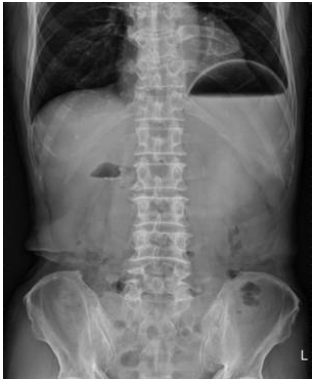

32 75 歲男性,最近食慾變差,腹脹、上腹痛且有反胃、嘔吐的情形,其腹部 X 光如下,最為適當的診 斷為何?

(A)消化道穿孔(perforation) (B)胃出口阻塞(gastric outlet obstruction) (C)大腸腫瘤(colon tumor) (D)糞便阻塞(stool impaction)